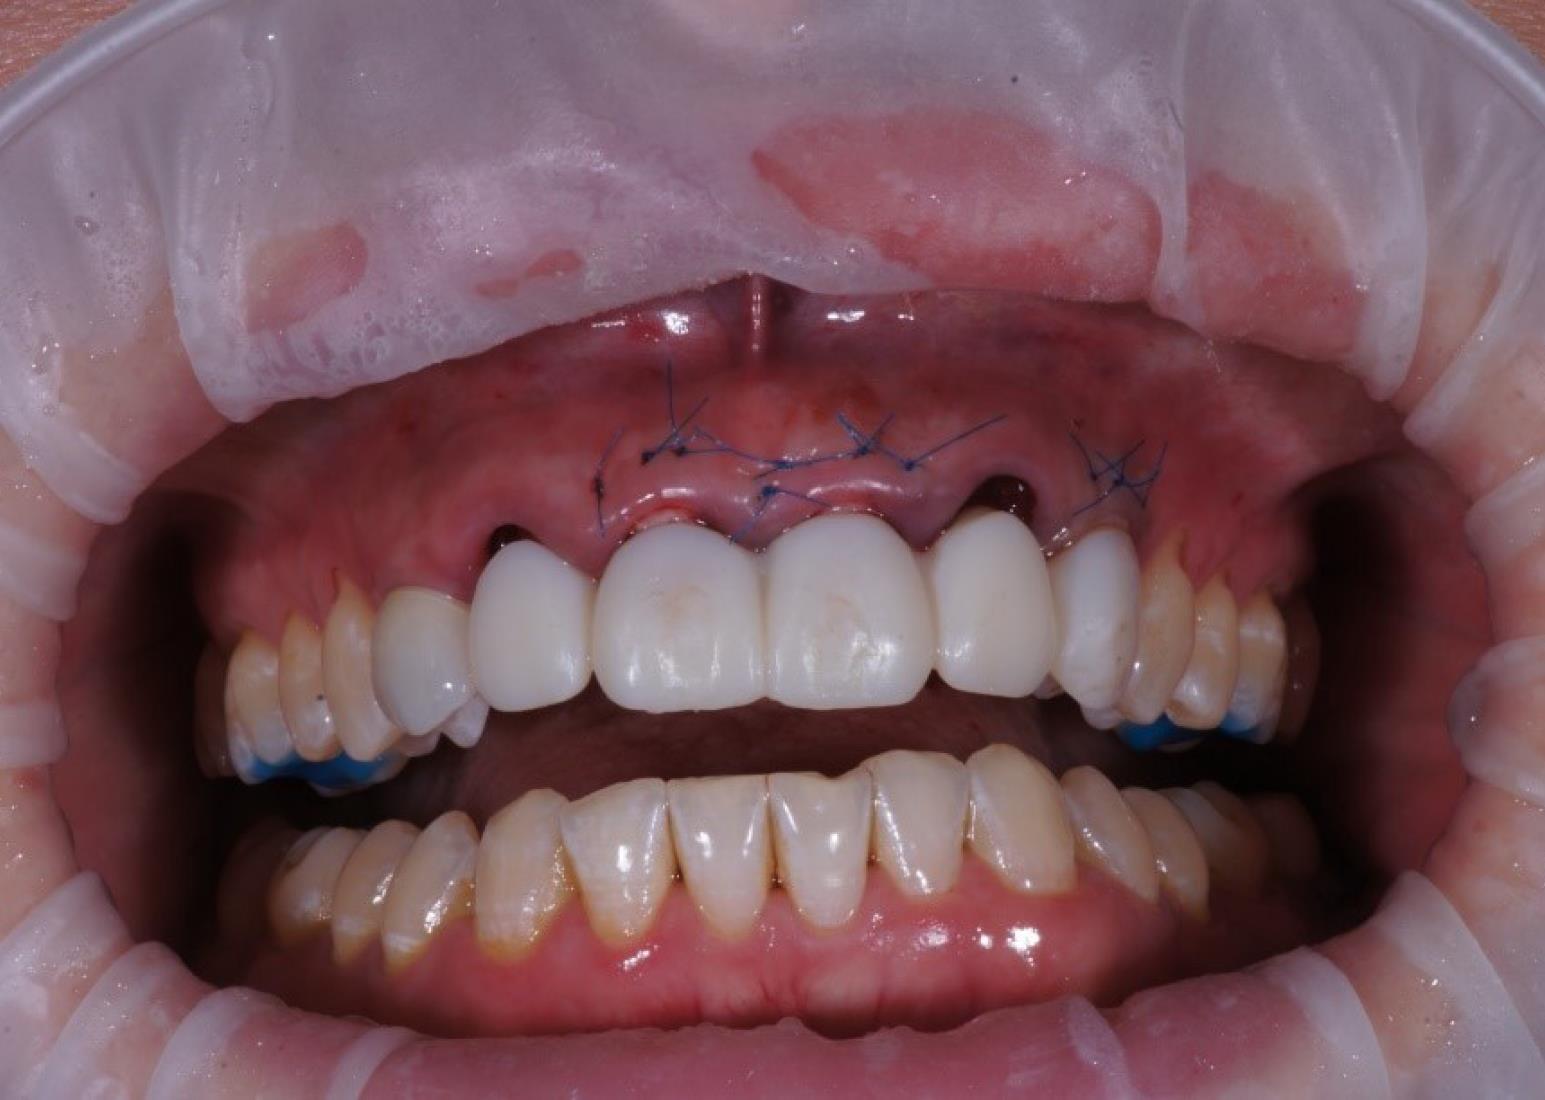

Orthopedic protocol (provisional phase)

The provisional crowns were placed immediately after the completion of the entire surgical phase (Figures 5 and 6). A temporary abutment and bis-acrylic material for provisional restorations in combination with a light-curing composite filling material were used for their fabrication. The sterile titanium provisional abutment was isolated with a collagen sponge to retain the blood clot. The alveolus was isolated with a rubber dam to apply the filling material and prevent infection. The structure was completed outside the oral cavity - modernizing the shape of the sub- and supragingival parts of the orthopedic structure to create a proper fit along the upper contour of the socket and create a space for a blood clot to protect the bone structure. All provisional orthopedic prostheses loaded immediately after implantation had a transocclusive fixation method.

Figure 5.

Soft tissue and gingiva former placement